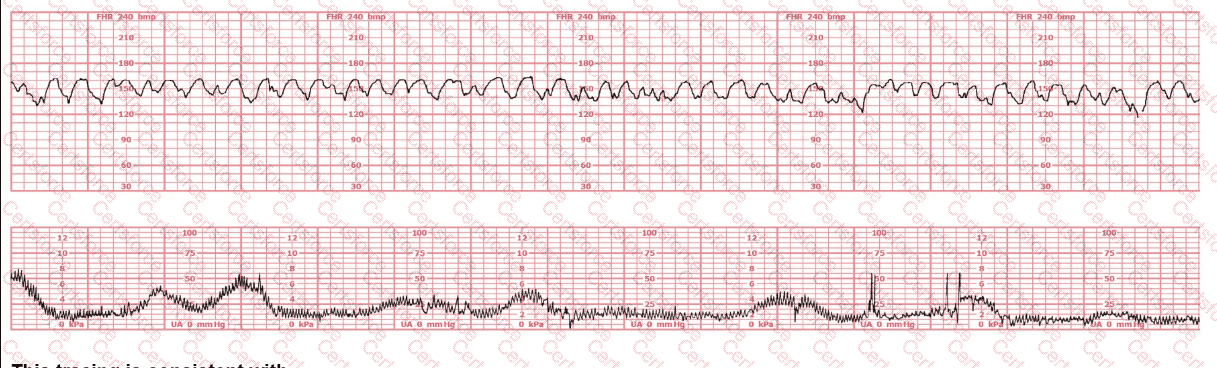

(Full question statement)

This tracing is consistent with:

Question # 27

Options:

Atrial flutter

Effects of butorphanol administration

Fetal-maternal transfusion